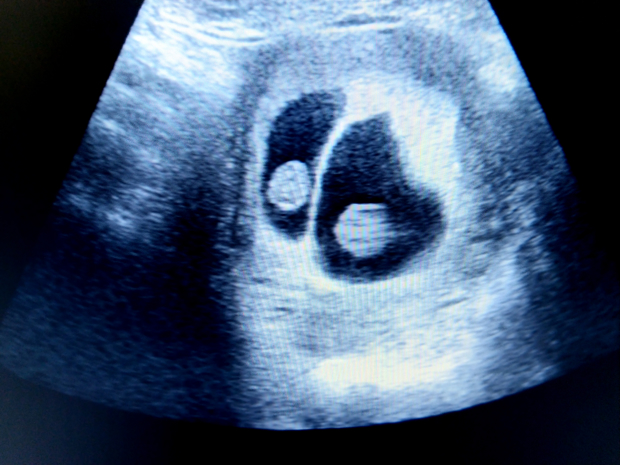

Quelles sont les recommandations lors d’une grossesse multiple?

Un plus grand apport alimentaire est nécessaire pour une grossesse multiple. Les besoins en énergie, protéines, vitamines et minéraux sont évidemment plus élevés puisqu’il y a 2 fœtus (ou plus) et que ces derniers se font compétition pour obtenir les éléments nécessaires à leur développement.